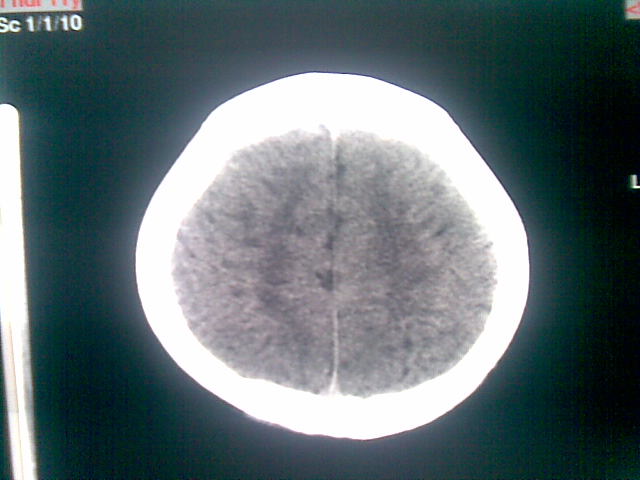

以下是引用随光逐影在2010-1-5 16:32:00的发言:[br]1)鞍上池囊性占位性病变,不排除蛛网膜囊肿可能;建议行mri检查。2)脑积水。

以下是引用yangyang2000在2010-1-5 20:41:00的发言:[br])鞍上池囊性占位性病变,不排除蛛网膜囊肿可能;建议行mri检查。2)脑积水

以下是引用yangyudong333在2010-1-5 21:28:00的发言:[br]1)鞍上池囊性占位性病变,不排除蛛网膜囊肿可能;建议行mri检查。2)脑积水。